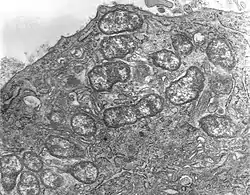

Orientia es un género de bacteria en la familia Rickettsiaceae.

Son parásitos intracelulares obligados, gram negativos presentes en insectos y mamíferos.

La única especie del género es Orientia tsutsugamushi, que causa la fiebre de los matorrales en humanos.[1]